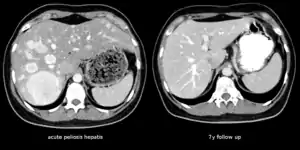

| The CT scan of a patient with peliosis hepatis (left): The follow-up CT (right) after 7 years shows full remission. | |